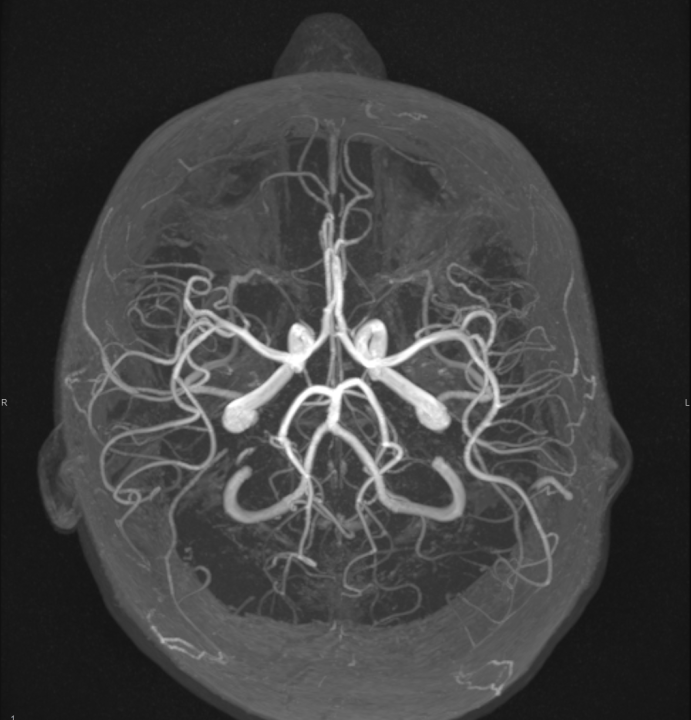

Ako su vam potrebni specijalistički pregledi mamografija, RTG, UZV, CT i MR, koji se inače koriste za dijagnostiku velikog broja zdravstvenih problema, možete ih obaviti već danas ili sutra.